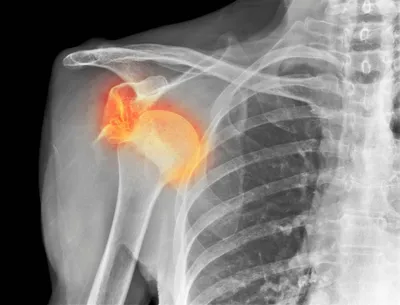

La luxation d'épaule au cabinet de kinésithérapie MMK entre la perfecture et la place Castellane à Marseille

La luxation de l'épaule par le cabinet de kiné MMK à Marseille 13006

La luxation d'épaule est une blessure fréquente, on la retrouve particulièrement chez les athlètes pratiquant des sports à contacts comme le rugby, le football, le handball. Pour les kinésithérapeutes du sport la gestion de cette blessure est une composante essentielle de leur pratique. La luxati...